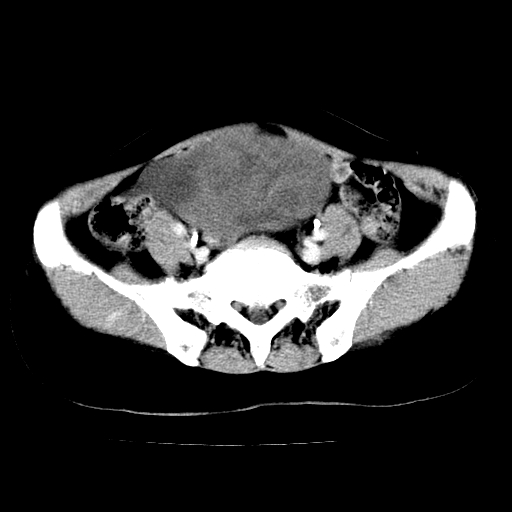

标题: CT24785:女,62岁,发现下腹部肿物半年。

女,62岁,发现下腹部肿物半年,下腹部不适。

考虑肠系膜间质肉瘤或脐尿管癌可能性大。

考虑回肠间质瘤,不排除卵巢癌可能。

考虑子宫平滑肌肉瘤可能性大。